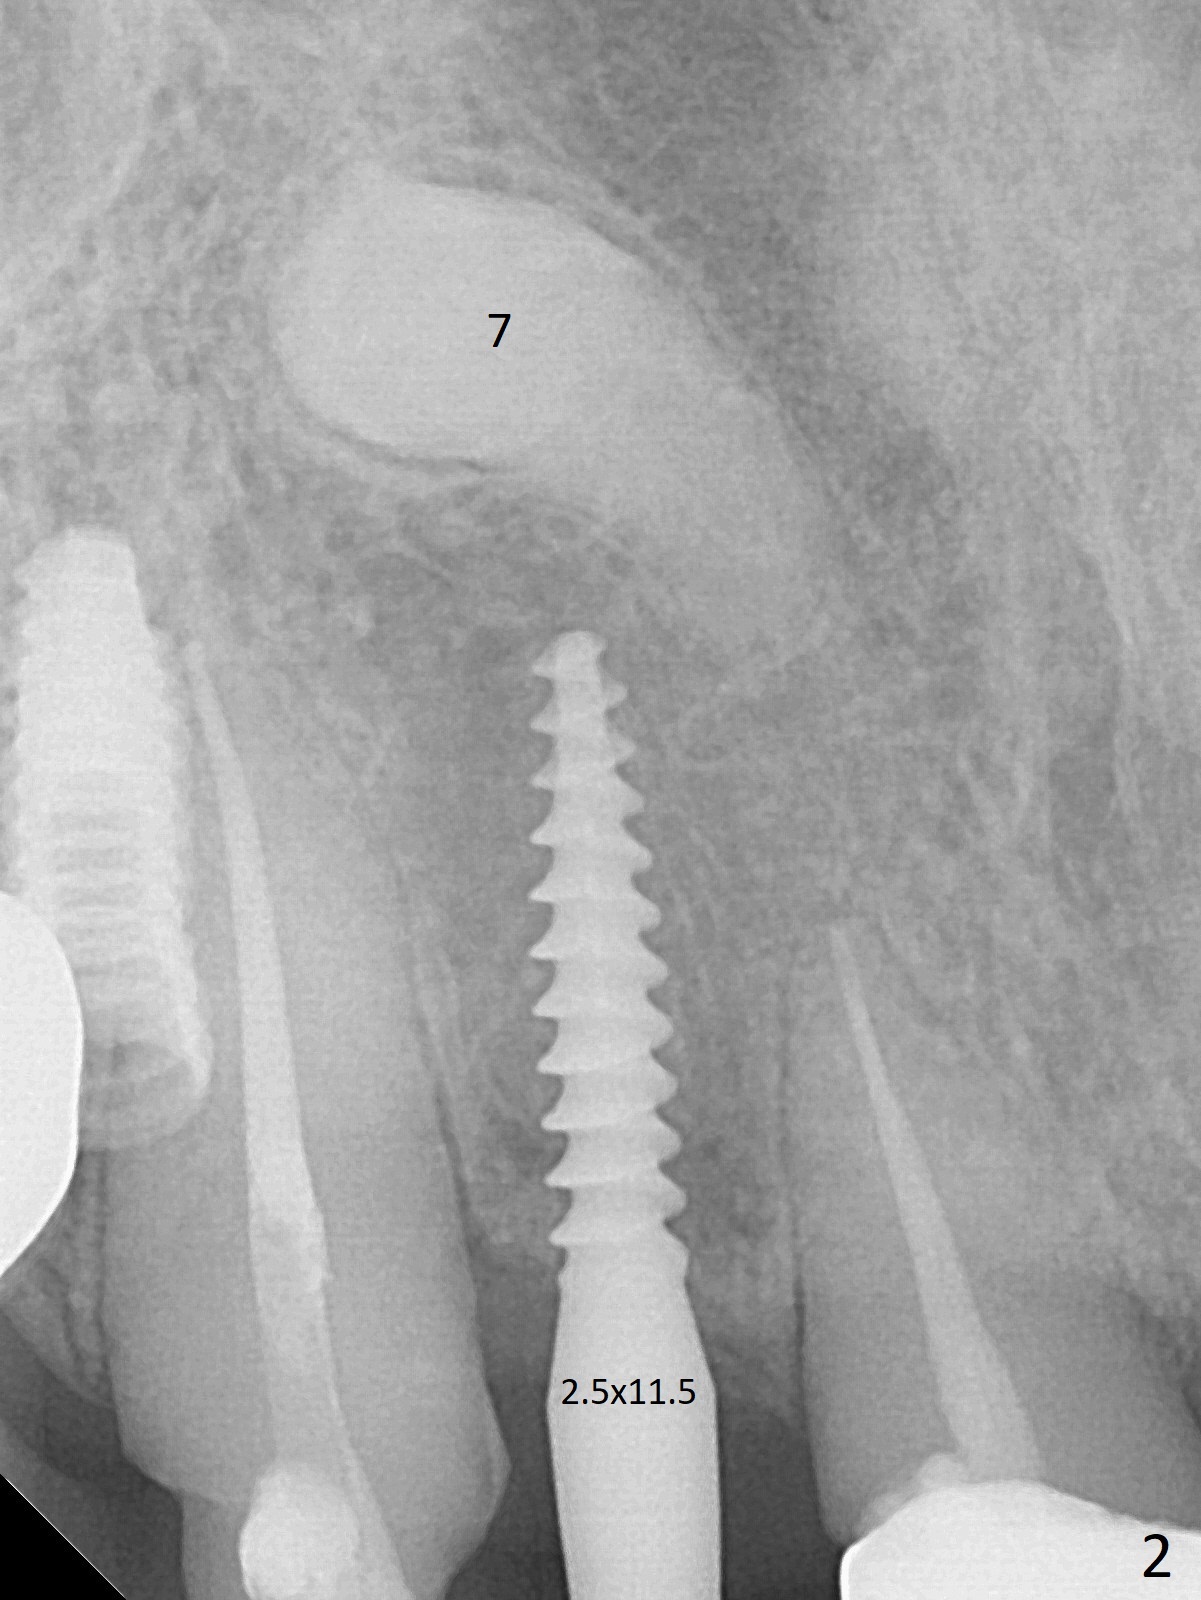

Two of 5x8.5 mm implants are placed at #2 and 3 with sinus lift using water ballooning technique; to avoid invading the neighboring root tips, an intraop PA is taken with a 2.2x11.5 mm drill at #5 (Fig.1). When a 2.5x11.5 mm 1-piece implant is placed at #7, there is 2.4 mm clearance from the impacted tooth (Fig.2). Following 1 mm deeper placement of the 1-piece implant, CT is taken to make sure that the threads are completely covered palatally (Fig.5 P). Interesting is that the sinus membrane is thickened at #2 and 3 (Fig.3 M), as compared to the clear sinus before surgery (Fig.3'). Bone graft is limited in the sinus (Fig.3 arrowheads). The implant at #5 (3.5x11.5 mm) is precisely placed subcrest bucco(B)-palatally (Fig.4). Since the limited field viewed CT does not cover the implant at #2 (Fig.3), immediate postop PA is taken (Fig.6). In fact all of the implants are placed subcrestal, as shown by intraoral X-ray 4 months postop (Fig.7-9). The abutments at #2, 3 and 5 are retorqued (30 Ncm) after crowns' try in and adjustment (Fig.10,11). There is a vertical gap between the implant and abutment at #2 (Fig.11 ^) and a horizontal one at #5 (<). There is apparently no bone loss 1 year 5 months post cementation (Fig.12).